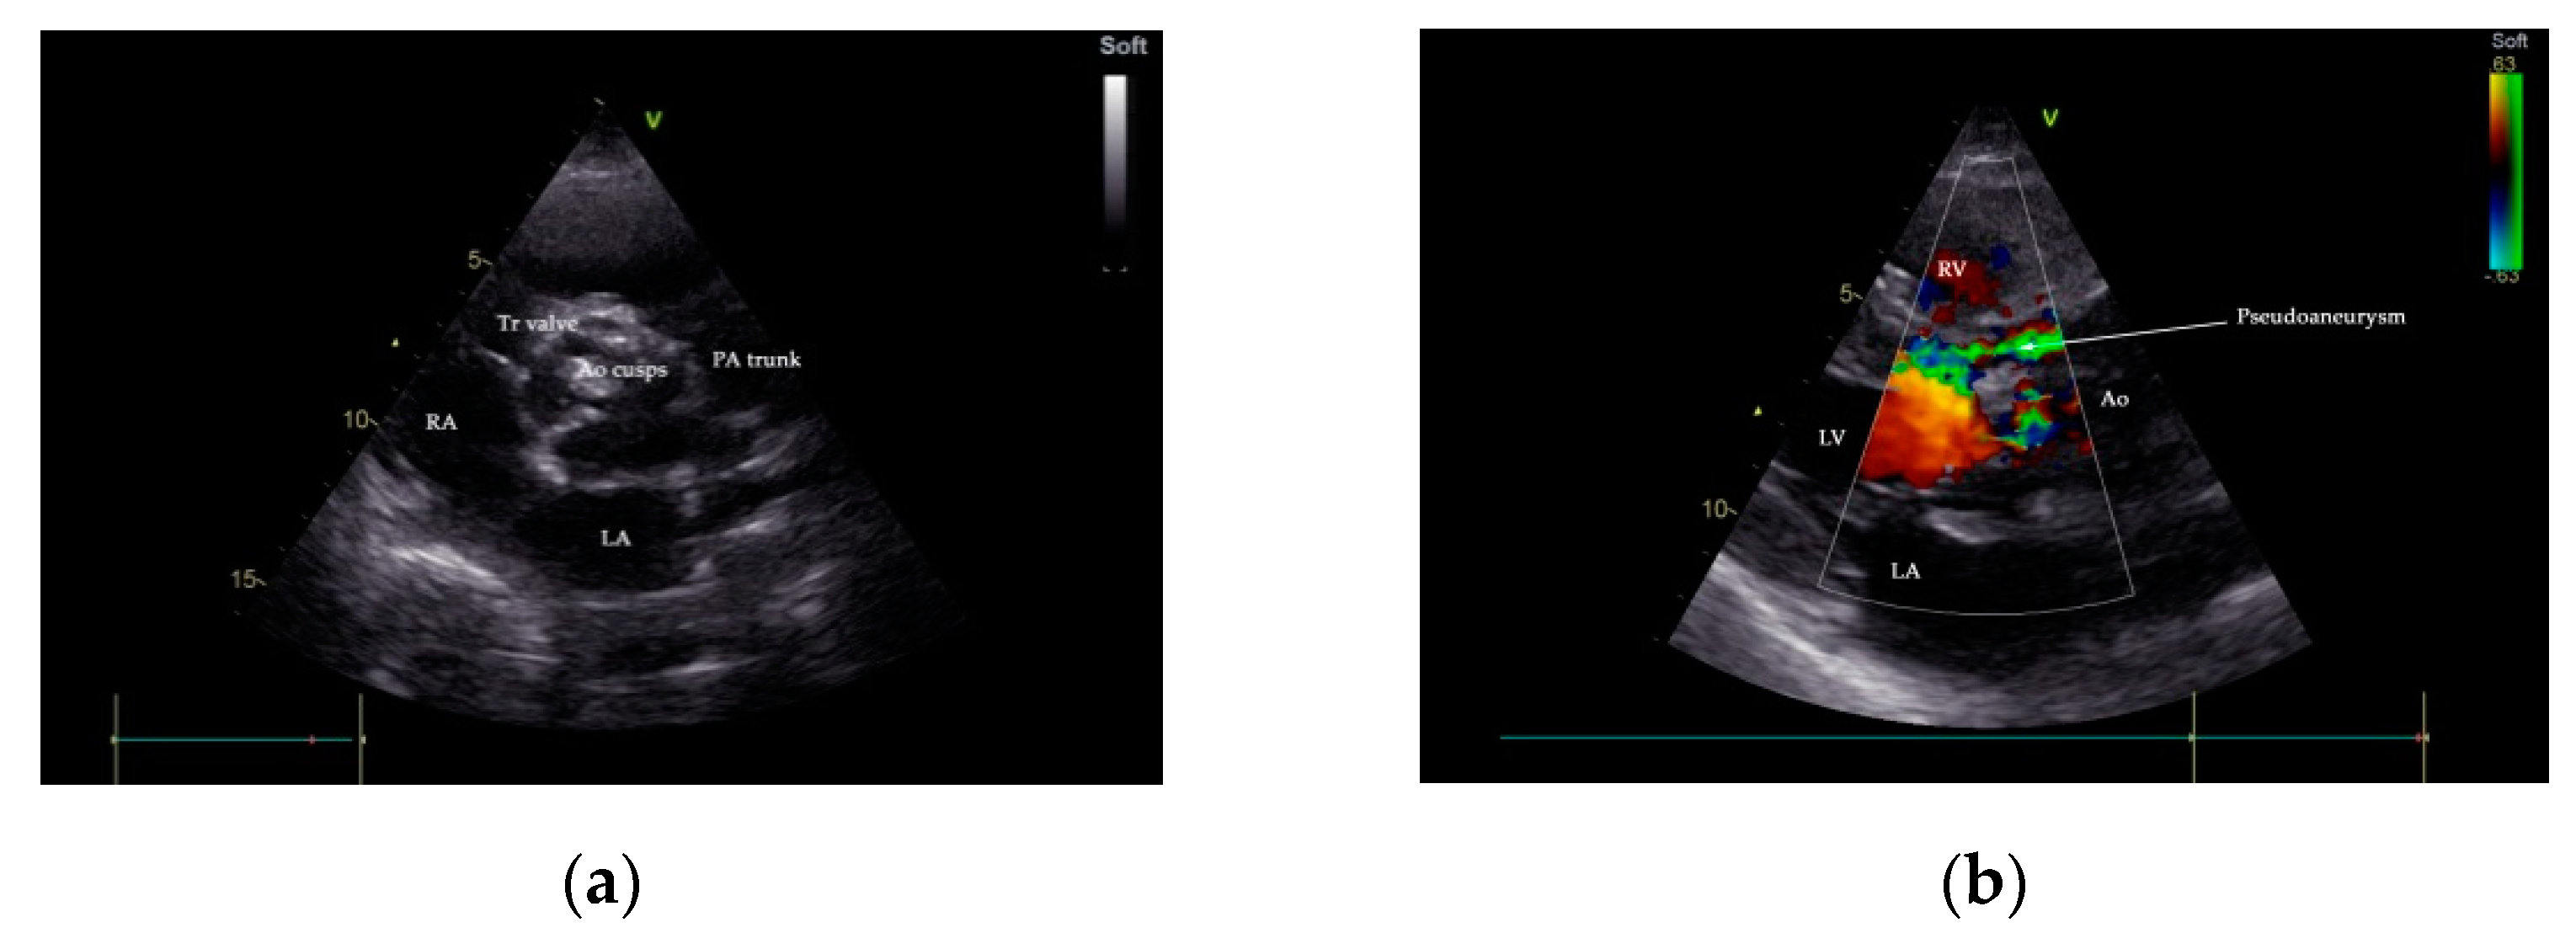

Two-dimensional transthoracic and transesophageal echocardiography (TTE and TOE, respectively) were performed (GE VividTM E9 ultrasound system, GE Healthcare, Boston, MA, USA). Analysis of TTE images denoted a large P-MAIVF (60 mm × 6 mm), LVH, normal dimensions of the left ventricle with an LV ejection fraction of 65% (modified Simpson’s biplane method), bicuspid aortic valve, and severe aortic stenosis (peak velocity: 4.8 m/s, gradient of 91/60 mm Hg, AVA: 0.51 cm2/m2). Mild aortic and mitral regurgitation were noted. A 5 mm × 7 mm vegetation was identified at the level on the anterior aortic cusp (Figure 2 and Figure 3). Echocardiographic assessment did not confirm pericardial effusion or the presence of pulmonary hypertension (Supplementary Movie S1).

Figure 2.

Transthoracic echocardiography (TTE), parasternal short-axis-base view, showing a heavily calcified aortic valve with possible vegetation (a); communication between LVOT and P-MAIVF is shown by color flow Doppler, parasternal-long axis view (b). Ao—aorta, LA—left atrium, LVOT—left ventricular outflow tract, PA—pulmonary artery, P-MAIVF—pseudoaneurysm of the mitral-aortic intervalvular fibrosa, RA—right atrium, RV—right ventricle, Tr—tricuspid valve.